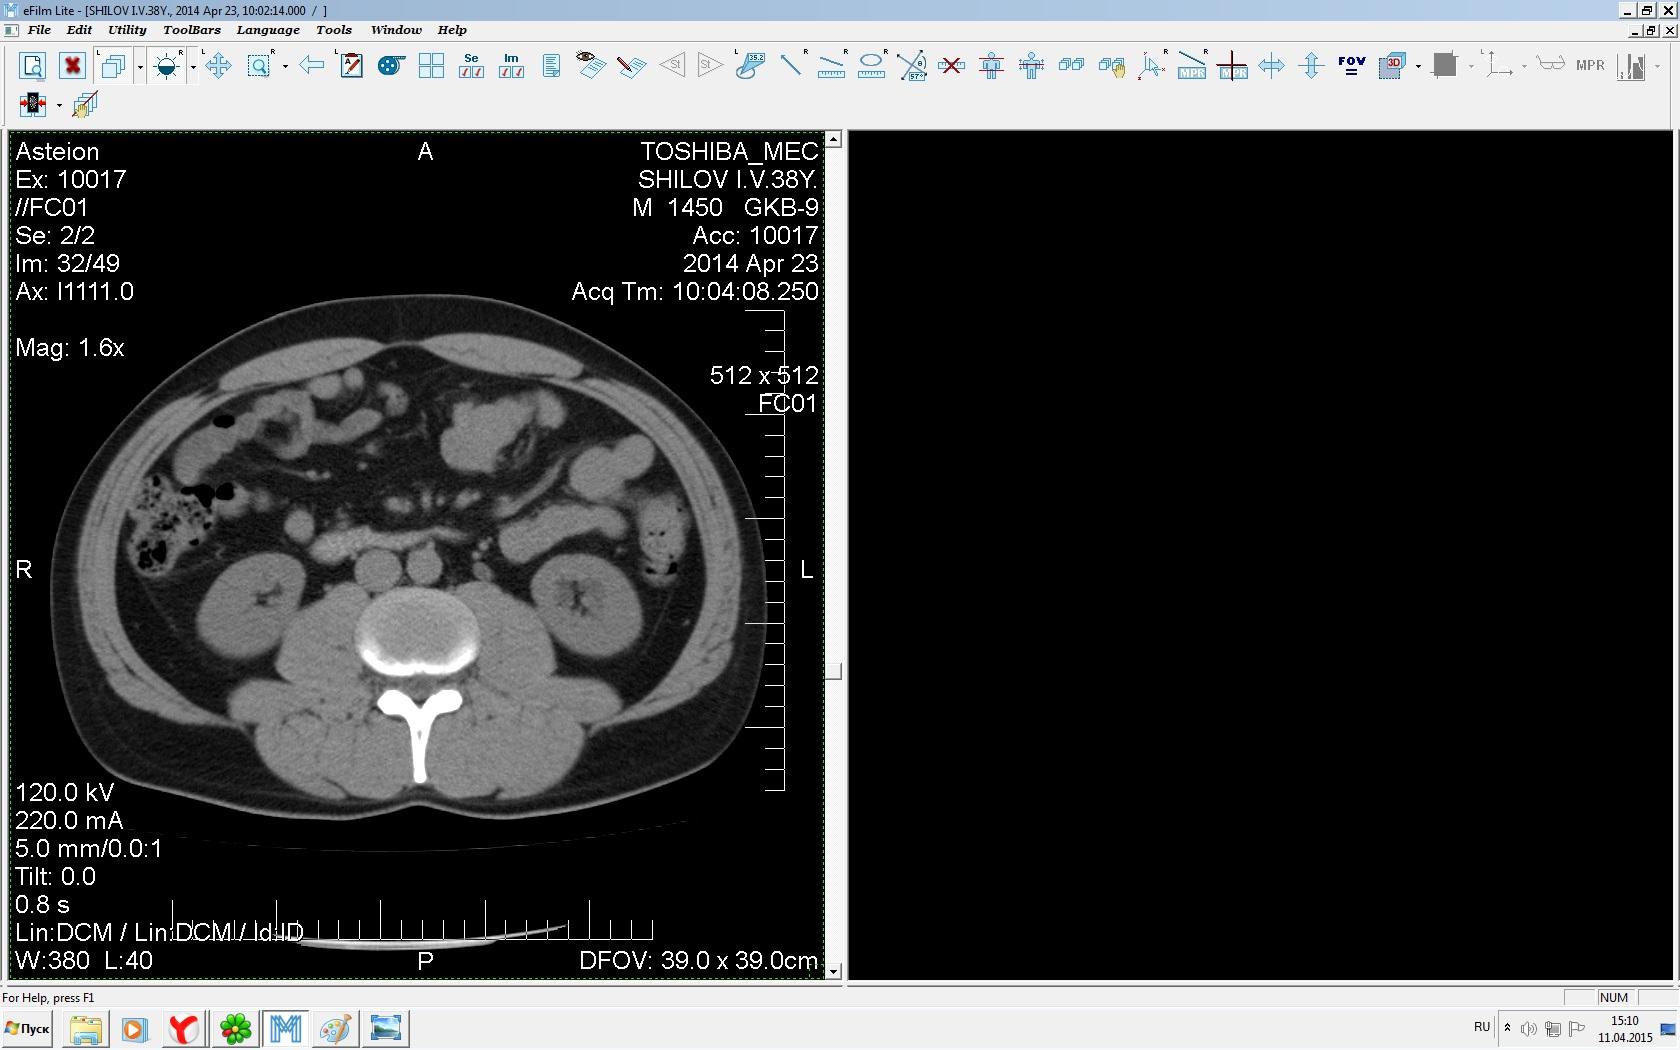

Здравствуйте. У меня киста левой почки. Из заключения: левая почка увеличена, деформирована за счёт наличия в среднем сегменте округлого жидкостного +6, +15 HU образования 66х53 мм, деформирует, поддавливает чаше-лоханочную систему. Сосудистые ножки структурные. В урологии мне сперва предложили лапароскопию, когда я лёг на операцию - изменили на полостную в связи со сложностью. Потом сказали что шансов вырезать кисту без почки практически нет. Даже если кисту удалить чудесным способом, то почка всё равно сложится и не будет работать. В итоге операцию отменили. Скажите, пожалуйста, есть ли современный метод удалить кисту и сохранить почку в моём случае? Томография почки в приложениях. Заранее благодарю.

Эту кисту можно просто пропунктировать, аспирировать и склерозировать - под местной анестезией. Ничего сверхестетственного не определяется по данным КТ. Можете написать мне на почту. aristova-tatyana@mail.ru